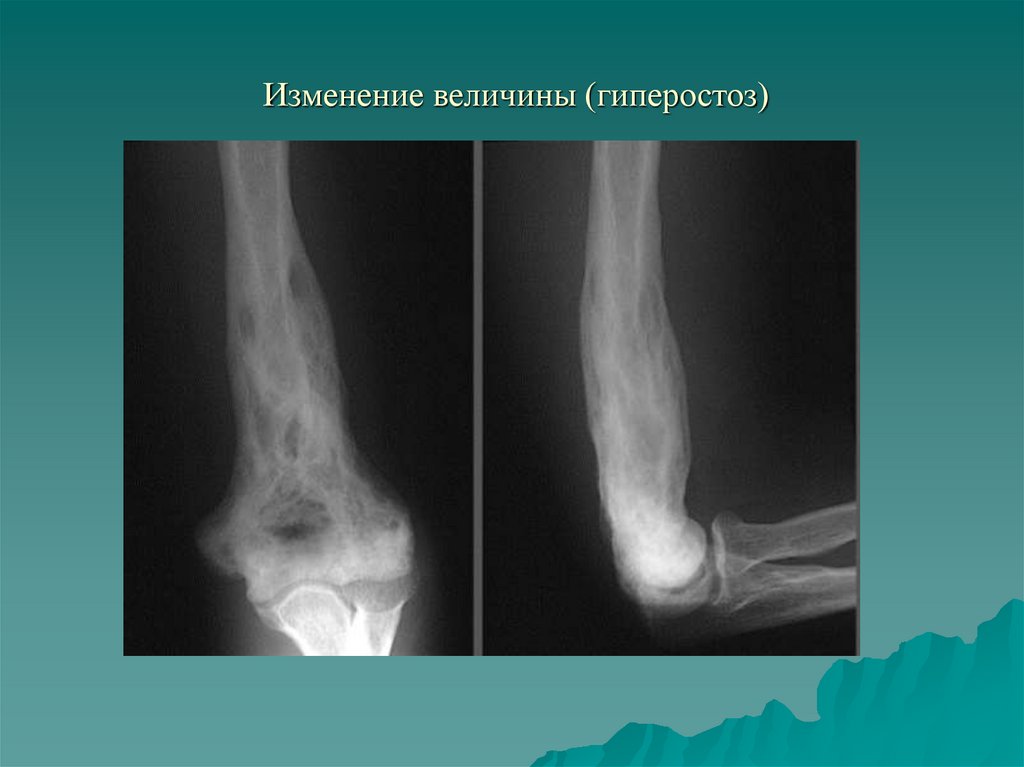

Изменение величины (гиперостоз)

4. I. Изменение величины и формы кости. Изменение количества

1.3. Утолщение кости - гиперостоз.

- Функциональный (рабочая гипертрофия);

- Воспалительный;

- Репаративный;

- Гормональный;

- Токсический (фосфор мышьяк);

- Врожденный (мелореостоз, гигантизм)

9. Изменение величины (гиперостоз)

10. Изменение величины (гиперостоз)